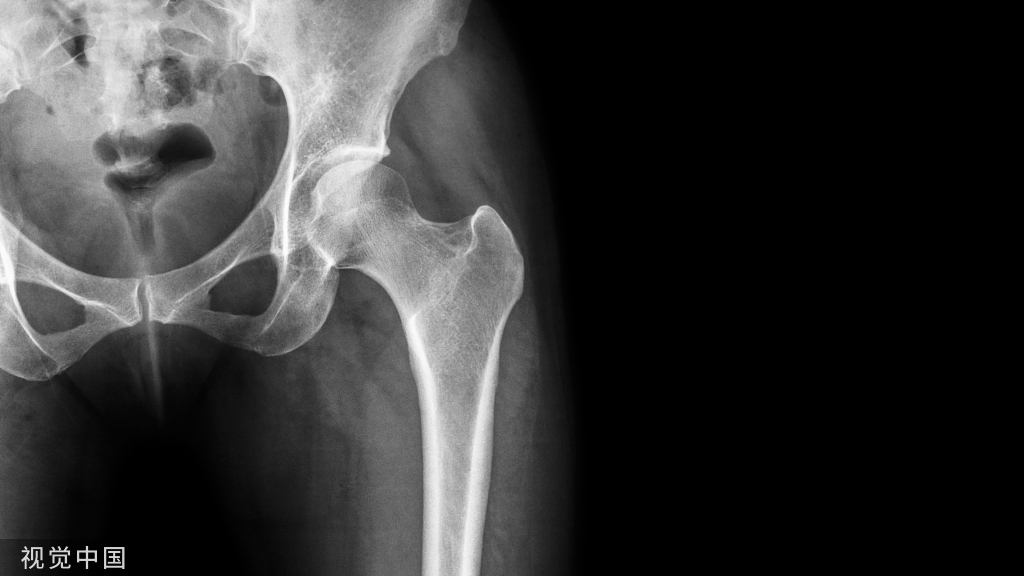

病史58岁男性,车祸后左侧骨盆疼痛。(A 58-year-old man with left sided pelvic pain following car accident.)

影像学表现股骨和骨盆骨可见多发小圆形硬化灶,X线片(a)和 CT图像(b)上都可见到左侧髂骨翼骨折。There are numerous small round sclerotic foci in the femurs and pelvic bones. Fracture of the left upper iliac wing is seen on both the radiograph (a) and CT image (b).